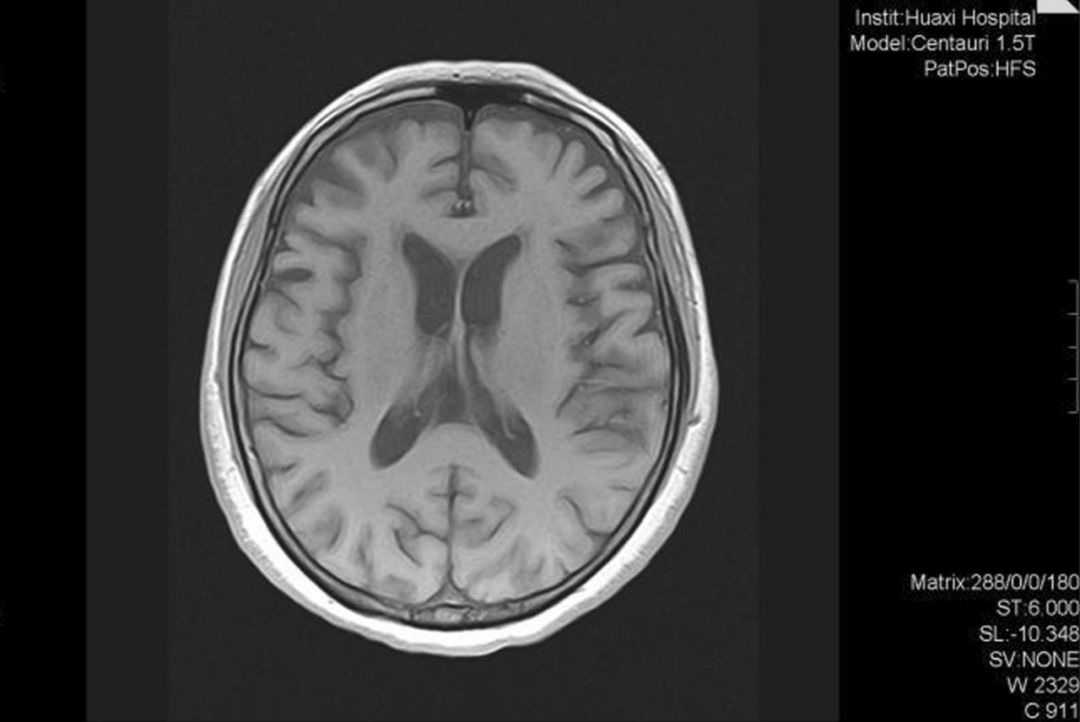

图3 2019年8月头部MRI示双侧额颞叶中度萎缩(Li X, et al. 2020)

出院后2个月随访,我们给患者进行了痴呆相关的基因检测,分析了53个与痴呆相关的基因,唯一检测到的突变为SORL1杂合突变(chr11:121340726, c.296A>G)。认知评估显示MMSE和MoCA得分均为20/30。予以美金刚

(10 mg/d),并停止服用盐酸苯海索,但在2019年7月随访时,患者的认知功能仍没有明显改善。2019年8月随访时,头部核磁共振显示额颞叶萎缩(图3),相比2018年加重,而18F-FDG PET/CT显示双侧额叶和尾状核代谢减退。MoCA得分为23/30,但ADL得分下降至31(表1)。患者无法完成许多日常生活活动。